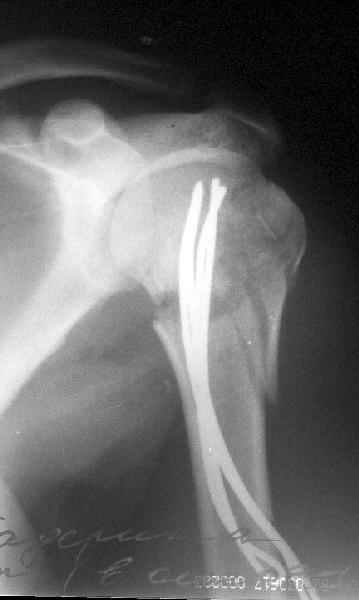

Клинические снимки - 3 недели после операции

с уважением М. Беренштейн

Посылаю послеоперационные Рг граммы.

Всего Доброго,

Евгений И Чекашкин

Поздравляю, получилось просто замечательно. Если можно, расскажи чуть подробнее, как делали - как вправляли, как вводили спицы, поворачивали ли их?

Спасибо за поздравления:-))

Я и сам доволен результатом. В предпоследнем письме я кратко описал ход операции - закрыто репонировать не удалось( 2 недели с момента травмы и 1 неделя после неудачной репозиции) после удаления пучков спиц, пришлось сделать - 2см разрез на уровне перелома и с помощью периостального элеватора (золотое правило механики) *одеть* головку на дистальный отломок.

Спицы проводил через старые отверстия, вращая пучок импактором- направителем при его введении в головку.